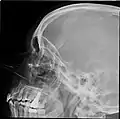

![]() مخطط جانبي للجيوب الجانبية الأنفية مخطط جانبي للجيوب الجانبية الأنفية | |